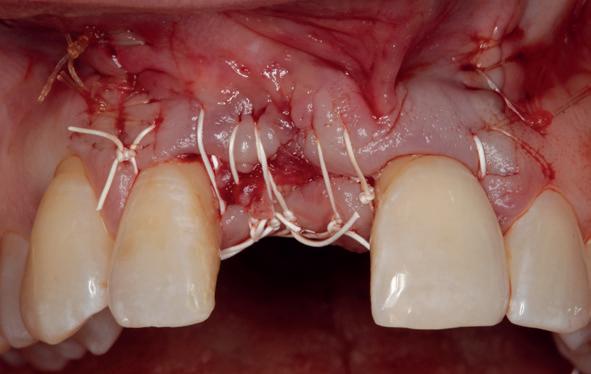

Lateraal van de implantaten wordt de kaak fors uitgebouwd volgens de Hybride GBR-techniek met Oragraft (allograft) van Lifenet die wordt vermengd tot een cocktail met BioOss (xenograft) van Geistlich, autoloog geoogste botsnippers en verzameld bloed uit het wondgebied. De botgraft wordt bedekt met een Ossix (crossed linked) membraan en met Hyadent (hyaluronzuur) overspoten. De sinuslift wordt gelijktijdig met de laterale botopbouw volgens de Caldwell Luc methode uitgevoerd en de uitgeprepareerde holte opgevuld met de botgraft. De flaps worden eerst horizontaal ontlast (gemobiliseerd) en vervolgens naar elkaar toe gehecht met vicryl rapide. Daarbij wordt gebruikgemaakt van horizontale matrassen, zodat de wondranden passief tegen elkaar

komen te liggen en de flaps primair gesloten kunnen worden. Het passief sluiten van een flap voorkomt wonddehiscenties in de genezingsfase die als complicaties kunnen optreden en botregeneratie verstoren. Daarnaast wordt bij een wonddehiscentie het risico op infectie van de graft sterk verhoogd waardoor het gewenste resultaat niet kan worden bereikt. Afstoting van graft materiaal komt dan veelvuldig voor soms gecombineerd met abcesvorming als geen voorzorgsmaatregelen worden genomen. Complicaties moeten daarom nauwlettend gevolgd worden totdat ze verdwenen zijn. De patiënt krijgt na chirurgie postoperatieve instructies en adviezen over de postoperatieve zorg. Daarbij wordt ook de nadruk gelegd op het koelen (coldpack) en zijdelingse druk op de wang. Het blijkt dat koelen en het uitoefenen van druk op het operatiegebied oedeem en hematoomvorming grotendeels kunnen verminderen en soms zelfs kunnen voorkomen.

Twee weken later zie ik de patiënt terug voor controle van de eerste wondgenezing. De noodprothese mag de eerste twee weken niet gedragen worden en wordt tijdens de controle zorgvuldig aangepast aan de nieuwe situatie. Hiervoor wordt de prothese gedeeltelijk uitgefreesd en voorzien van een Soft Reliner materiaal. Te veel druk op de beide kaken moet ten alle tijden voorkomen worden en heeft effect op de ingroei van de botopbouw. De genezingsperiode duurt tenminste zes maanden voordat verdergegaan kan worden met de tweede fase: de abutment chirurgie. Hierbij wordt extra aandacht besteed aan het herstel van de gekeratiniseerde gingiva rondom de abutments. Dit komt ten goede aan de uitvoering van de mondhygiëne en dus de stabiliteit van de peri-implantaire mucosa. Deze ogenschijnlijk eenvoudige behandeling is essentieel voor de prognose van de implantaten op de lange termijn. Te weinig gekeratiniseerde mucosa maakt zelfzorg (borstelen/interdentaal reinigen) vaker pijnlijk of lastig, waardoor plaque en mucositis makkelijker kunnen ontstaan en blijven over de lange termijn. Dat kan bij patiënten die vatbaar zijn voor peri-implantitis zich vertalen naar crestaal botverlies rondom implantaten. Gek genoeg wordt de essentie van het herstellen van de gekeratiniseerde gingiva rondom implantaten regelmatig genegeerd.